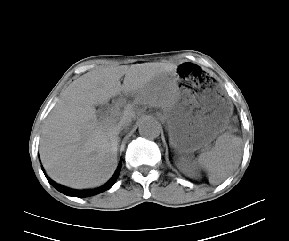

标题: CT19533:病变来源于哪?

患者,男,发现上腹部包块两月余。

病变位于肝胃间隙,实际就是位于小网膜囊(左肝下后间隙),呈轻度不均匀性强化,腹腔内及腹膜后见多发肿大淋巴结。所以我考虑肝胃间隙恶性胃肠间质瘤并淋巴结转移。

病灶强化不显著,灶周及腹膜后见多量淋巴结肿大,考虑淋巴瘤可能,其次考虑间质瘤

强化后病变与胃壁分界清楚,并且血供不是来源胃壁血管。考虑胰腺颈体癌并腹腔腹膜后淋巴结转移。

肝胃韧带内及腹膜后可见多发增大的淋巴结影,首先考虑转移.